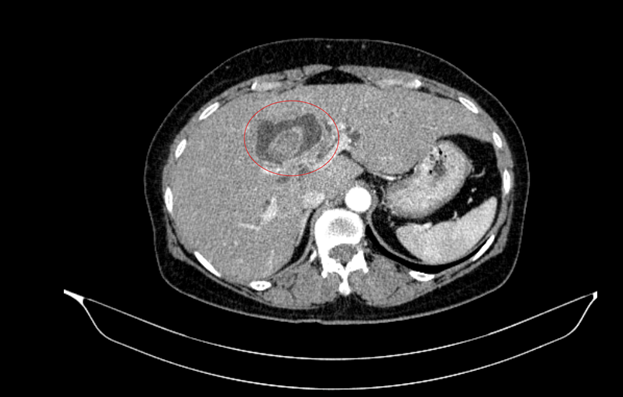

Hình ảnh sỏi đường mật tạo ổ áp xe gan - đường mật gan trái (vòng tròn màu đỏ) trên phim chụp cắt lớp vi tính - Ảnh: BVCC.

Theo đó, bệnh nhân nữ 59 tuổi nhập viện với biểu hiện vàng da, ngứa và đau vùng hạ sườn phải kéo dài. Kết quả chụp chiếu cho thấy tổn thương đường mật trong gan kèm sỏi và tình trạng giãn đường mật.